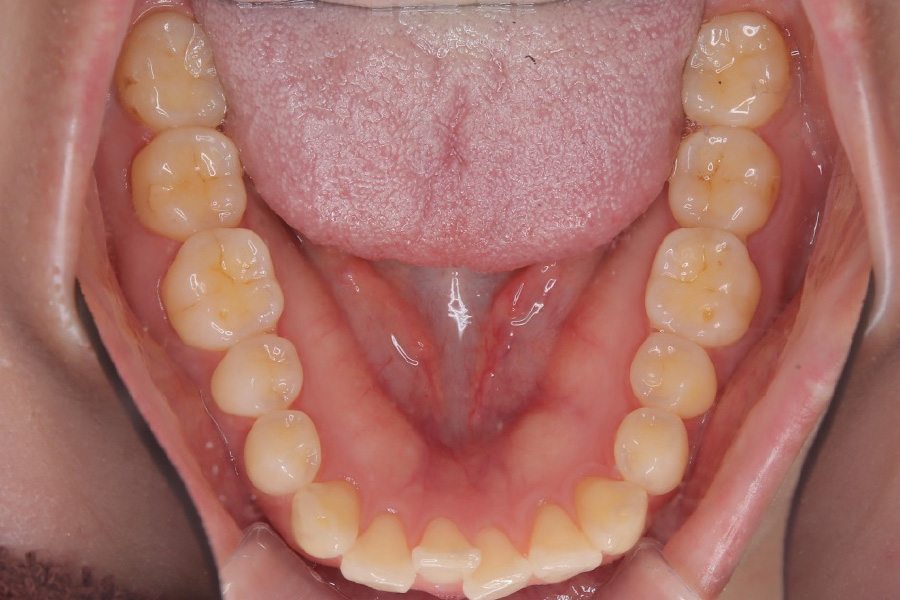

【20代女性】

歯のガタつきを

インビザライン矯正で治療したケース

治療後

主訴 ガタつき

期間 2年

費用 220,000円〜660,000円

治療内容 インビザライン矯正

非抜歯

治療に伴うリスク 矯正終了後は、リテーナーを指示通りに使用し、歯の後戻りを防ぐ必要があります。